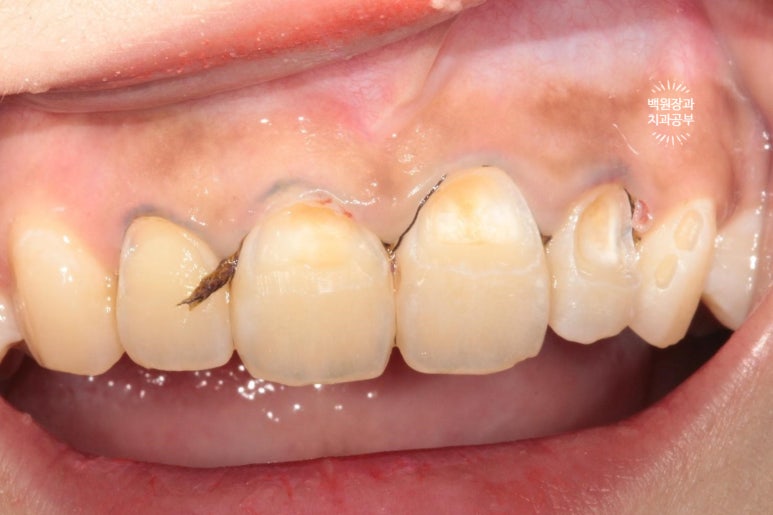

지금 잇몸 상태가 치석제거와 잇몸치료를 모두 완료한 직후입니다.

흡연으로 인한 약간의 잇몸 착색은 있지만, 붉고 부어 있었던 잇몸은 온데간데 없고, 너무나 깨끗한 잇몸상태를 되찾았죠...? 잇몸의 색깔은 선홍색으로 돌아왔고, 날씬하고 얇아진 모습입니다.

이것이 바로 잇몸치료의 위엄입니다!.. 치주과 전문의가 대표원장인 저희 치과에서 가장 많이 행하는 치료이기도 합니다.